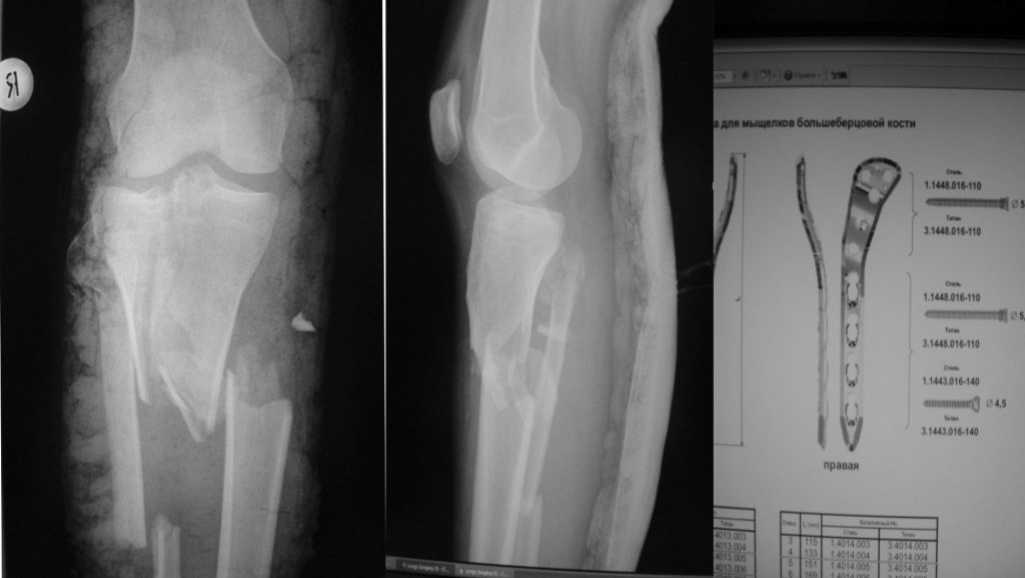

Большое спасибо! Благодаря Вашим советам я принял решение начать с артротомии, остеосинтеза мыщелков стягивающими винтами. С последующим остеосинтезом пластиной с угловой стабильностью. От артроскопии решил отказаться. Посоветуйте, пожалуйста, какова должна быть длина пластины (кол-во отверстий по диафизу). Это важно, так как пациентка приобретает конструкцию. И большого выбора на операции у меня не будет (максимум 2-3 пластины), поскольку в наличии наких конструкций в клинике нет. Фирма заказывает их в Польше. Мне нужно заказать конкретных 2-3 пластины и винты к ним. На снимке - выбраная мной пластина, но я не уверен насчет длины.

Длина пластин в зависимости от количества отверстий должна быть указана в каталоге. Соответственно можно померять почти прямо по снимку с учетом его увеличения. Похоже пластины на 8 диафизарных отверстий будет вполне идостаточно, если закажете ещзе на 10 и 12 - фирма не обидится - т.к. при наличии пластинм подходящий перелом появится быстро:)